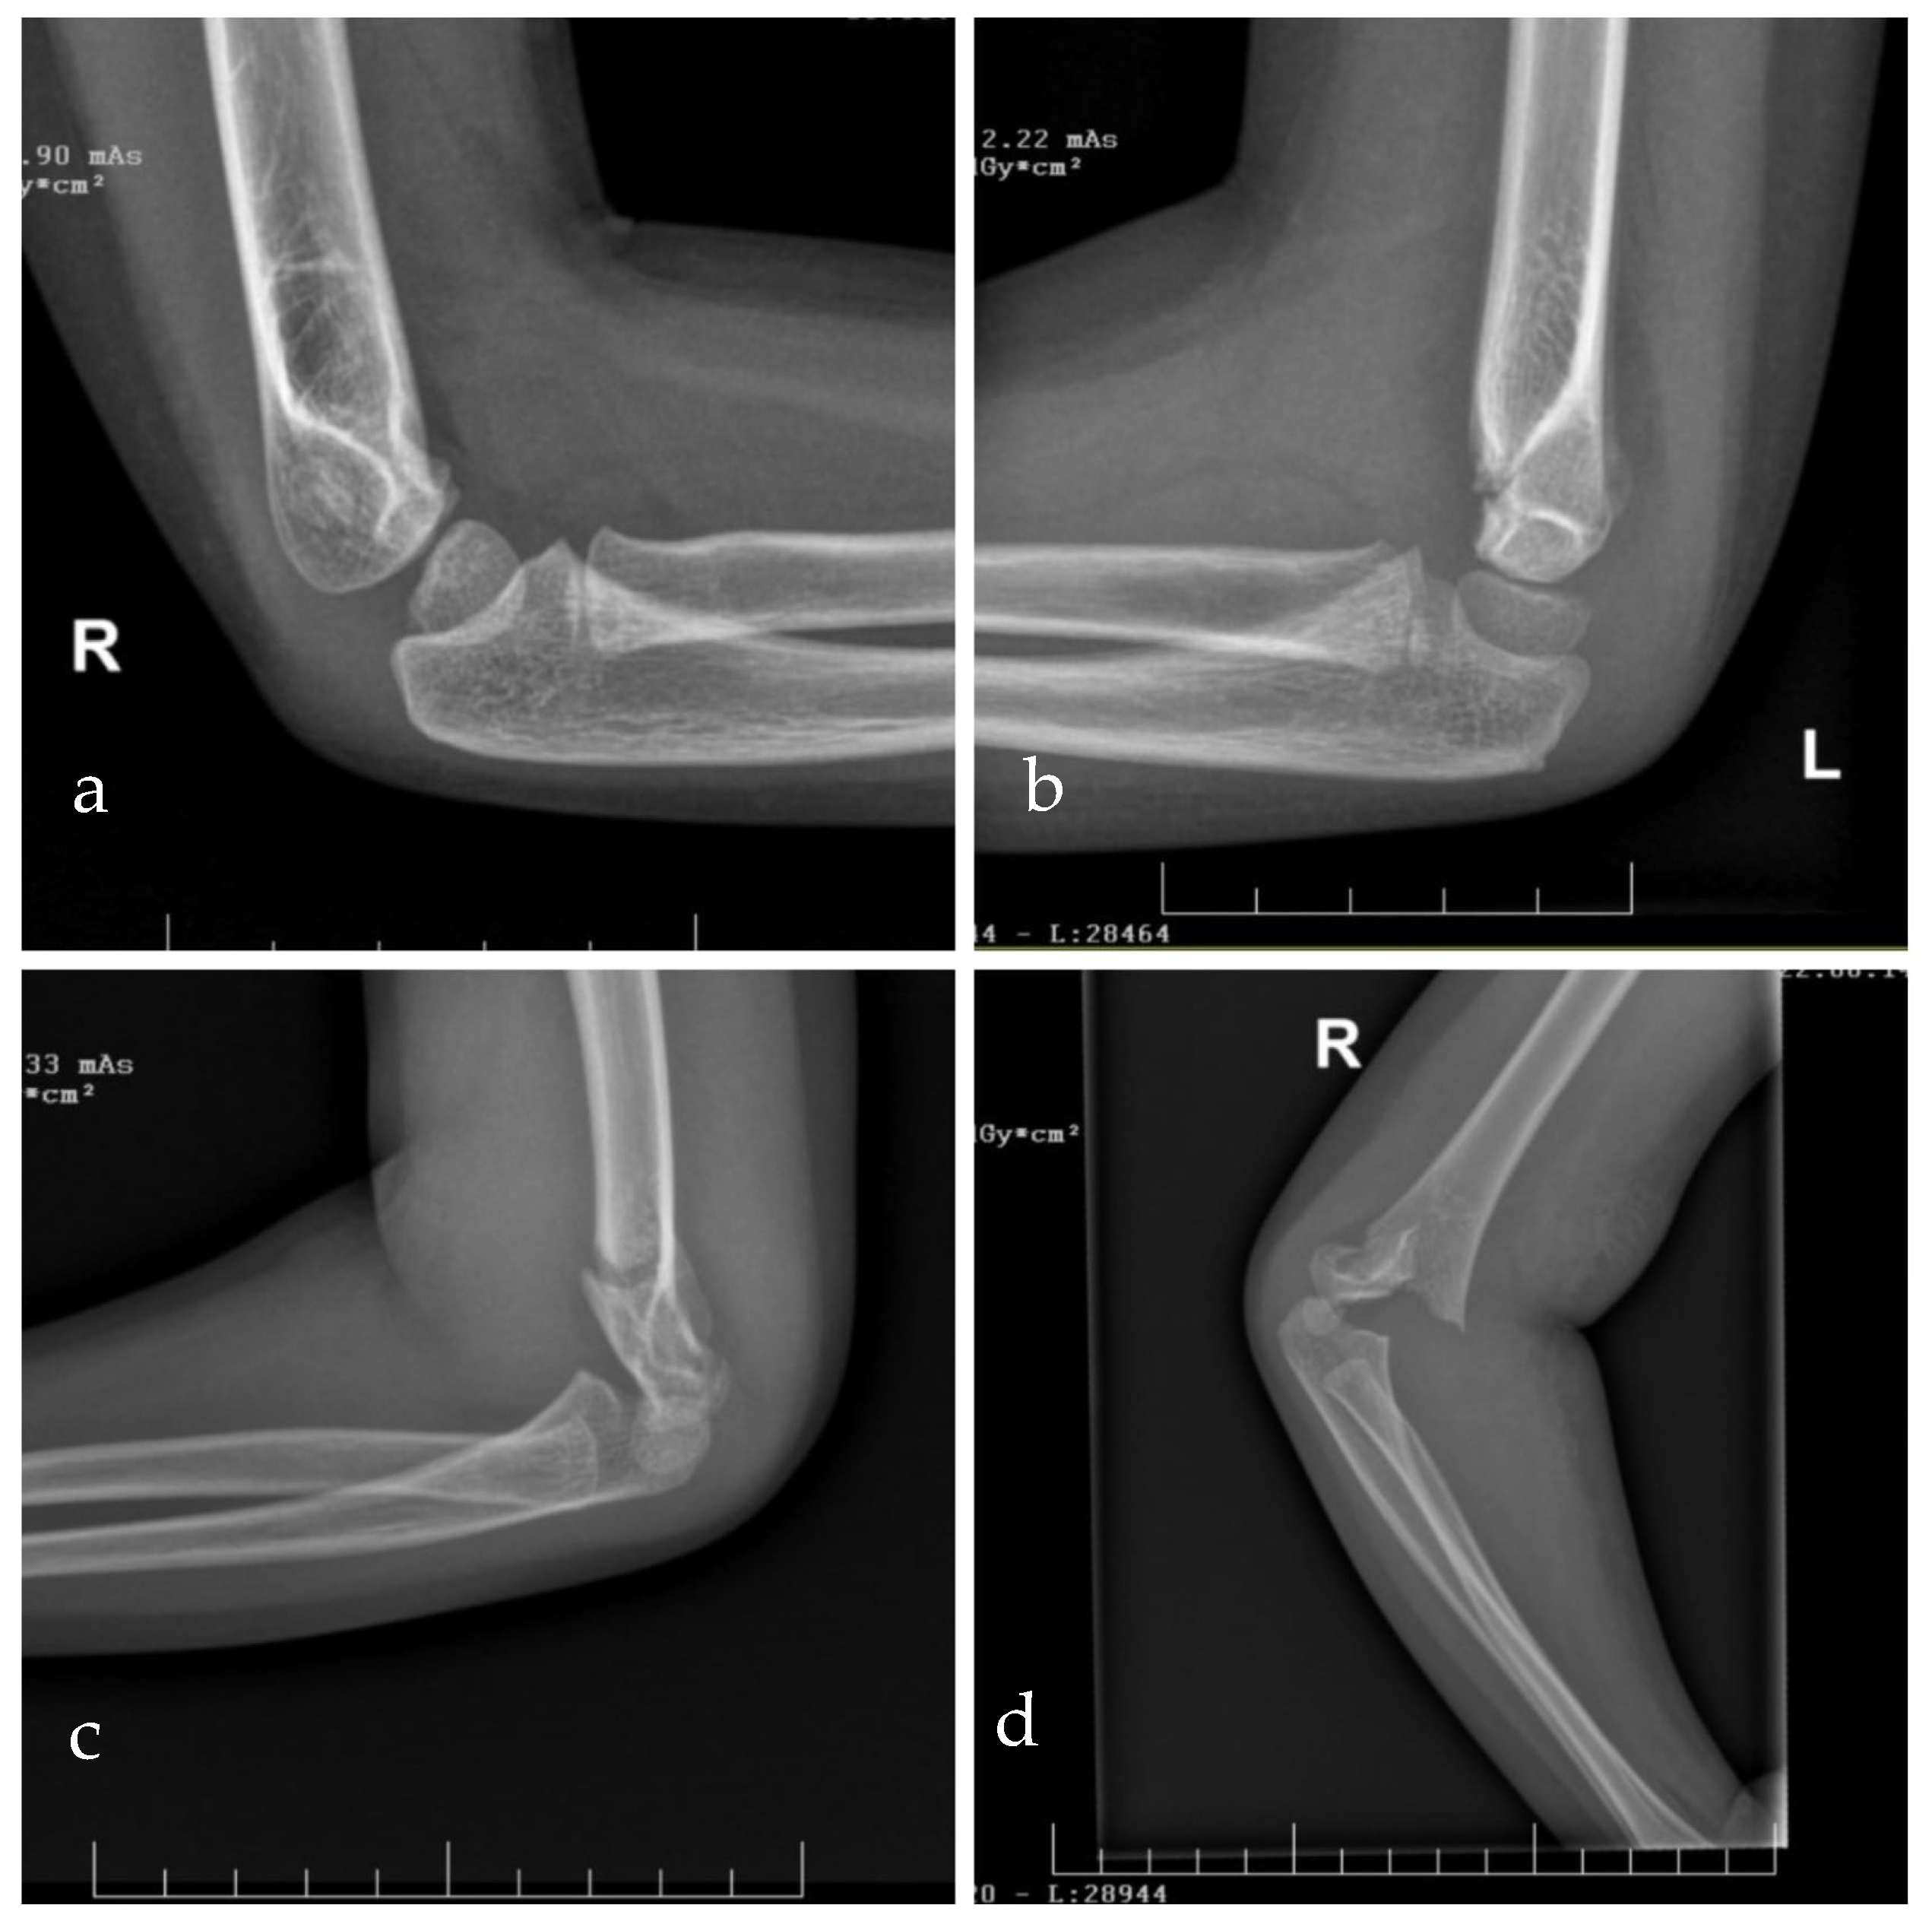

3.2. Evaluation of Supracondylar Humeral Fractures

3.2.3. Radiological Evaluation